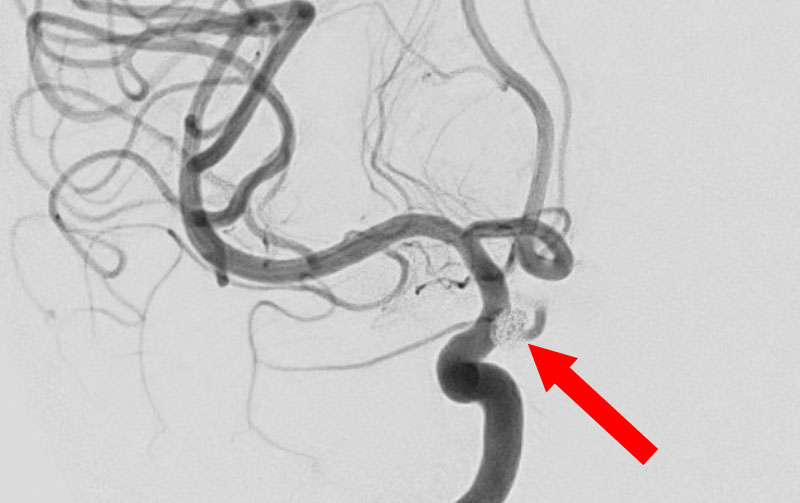

No.1631 手術後